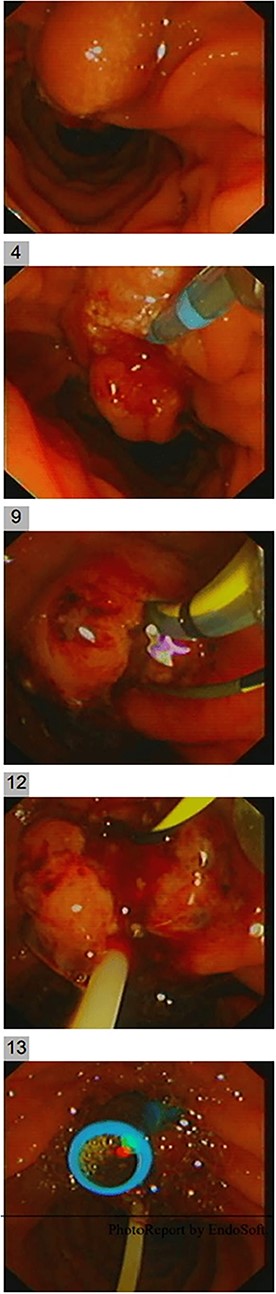

She had a CT chest to complete the staging workup, which was negative for metastasis. Eventually, she had a pancreaticoduodenectomy (Whipple procedure) with smooth postoperative recovery. The patient was discharged home on postoperative Day 7. The final histopathology came as moderately differentiated adenocarcinoma, pancreaticobiliary type with focal squamous differentiation (5%), invasion into the muscularis propria of the duodenum, and positive lymphovascular invasion with 1/12 LN positive for tumor deposits (Figs 3–6). All surgical margins were tumor-free. After a multidisciplinary meeting, the decision was made with proceed for adjuvant chemotherapy. Currently, she is on adjuvant chemotherapy, which she is tolerating well. Follow-up CT CAP at 3- and 6-month intervals postoperatively showed no evidence of recurrence or distant metastasis.

Microscopic image with H&E staining shows a tumor interface with normal liver parenchyma.